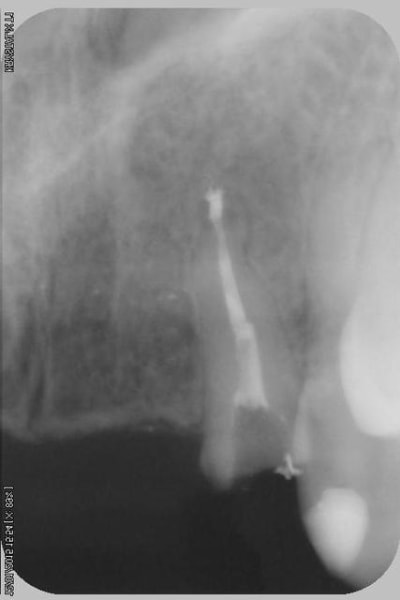

la suite

reconstitution, taille pour empreinte et provisoire (pas beau mais il sera remplacé)